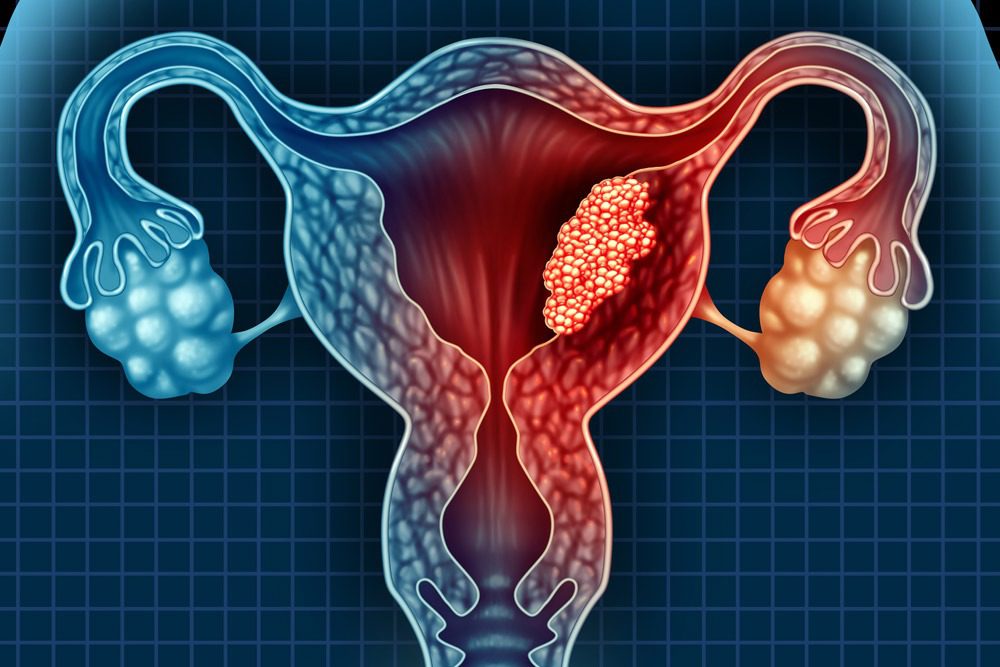

أورام المبيض من الحالات النسائية الشائعة التي تتطلب تشخيصا وعلاجا دقيقين. في الحالات التي يكون فيها التدخل الجراحي ضروريا ،

تشير أورام المبيض إلى النمو الغير طبيعي للخلايا في المبيضين، والتي تمكنها من التكاثر والنمو بشكل غير طبيعي.

هناك أنواع مختلفة من أورام المبيض، بما في ذلك الأورام الحميدة والحدودية والخبيثة.

تشمل سرطان المبيض، الذي يمثل تحديًا كبيرًا في مجال الصحة النسائية.

يعتبر سرطان المبيض صعب التشخيص في مراحله المبكرة،

وعادةً ما يتم اكتشافه عندما يكون قد انتشر في مراحل متقدمة.

يمكن أن يسبب سرطان المبيض في أعراض مثل الألم في منطقة الحوض، والانتفاخ، والتغييرات في نمط الدورة الشهرية، وفقدان الوزن غير المبرر، و تغيرات في عادات التبرز.

لذلك ، فإن فهم أورام المبيض والورم الليفي في الرحم يعد أمرًا بالغ الأهمية للنساء. يتطلب التشخيص المبكر والتدخل العلاجي الفعال التعاون بين الأطباء والمتخصصين في مجال الصحة النسائية. من خلال توفير المعلومات الموثوقة والدقيقة حول هاتين الحالتين وتشجيع الكشف المبكر، يمكن تحسين النتائج الصحية وتعزيز جودة الحياة للنساء المتأثرات بأورام المبيض والورم الليفي في الرحم